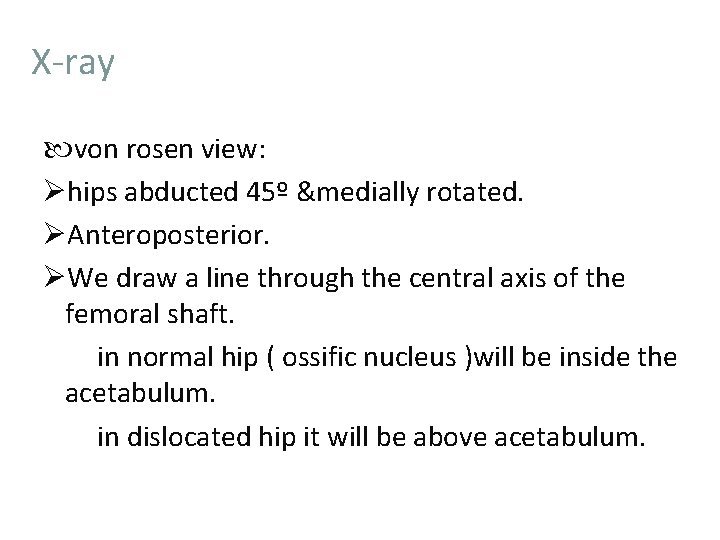

Developmental Dysplasia Of The Hip DDH Definition Dysplasia

Developmental Dysplasia Of The Hip DDH Definition Dysplasia

Developmental Dysplasia Of The Hip DDH Definition Dysplasia

Developmental Dysplasia Of The Hip DDH Definition Dysplasia

Developmental Dysplasia Of The Hip DDH Definition Dysplasia

Developmental Dysplasia Of The Hip DDH Definition Dysplasia

Developmental Dysplasia Of The Hip DDH Definition Dysplasia

Developmental Dysplasia Of The Hip DDH Definition Dysplasia